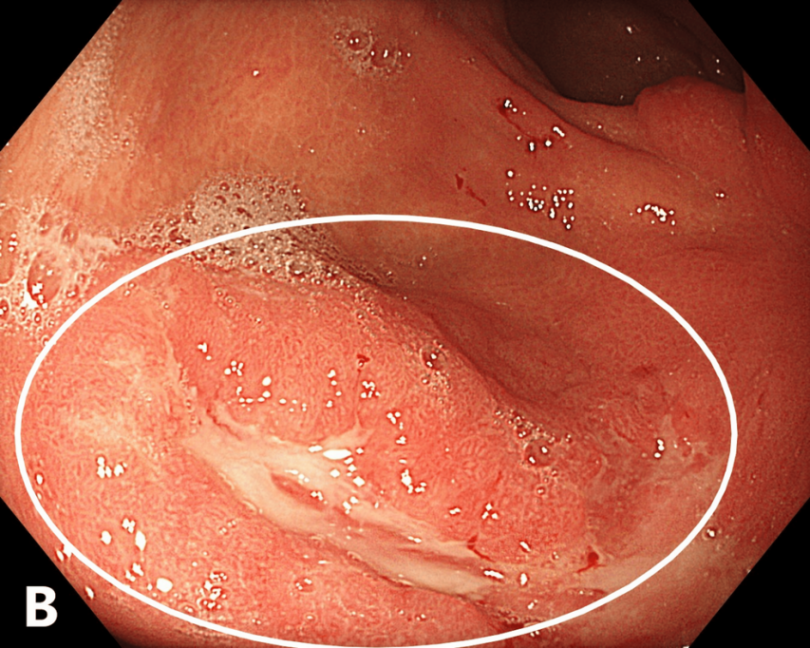

复查食管胃十二指肠镜(于初次检查后223天,即约7.4个月进行)显示:浸润性溃疡病变仍累及胃的大小弯,同时可见瘢痕形成及中度胃部变形,但未见突发型进展的证据(图3)。

图3. 溃疡区域伴纤维状涂层和周围水肿(内镜,2025年7月)